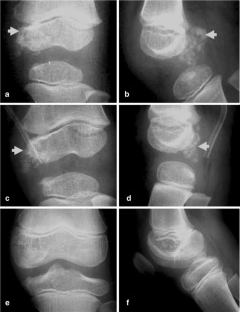

We found that, unlike in osteochondroma, DEH was radiographically not clearly separable from the underlying or host bone with preserved cortical bone and marrow continuity. The finding in the talus distinguished DEH from (osteochondroma-like) parosteal osteosarcoma, in which a radiolucent demarcation line clearly separated the tumor from the host bone. The DEH mass had a well-defined low to intermediate signal intensity on T1-weighted images and an intermediate to high signal intensity on T2-weighted images, with irregularity of the articular surface. Simple excision was performed in all patients. The excision was complete in six patients and incomplete in two patients whose lesions was juxta-articular in the ankle and articular in the knee, respectively. The residual mass slowly absorbed and vanished, resulting in mild flaring of the affected portion of the epiphysis. No local recurrence or complication was seen in any of the eight patients.

Although the radiographic signs of DEH are characteristic, (osteochondroma-like) parosteal osteosarcoma should be differentiated from DEH when there is a radiolucent separation line between the mass and host bone in the talus. Simple excision was effective in the management of DEH if the deformity was not complicated. Incompletely excised masses resolved and vanished with time.